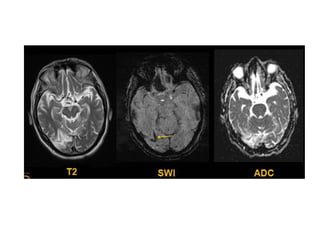

Thrombosis of deep cerebral veins

-The clinical presentation of thrombosis of the

deep cerebral venous system are severe

dysfunction of the diencephalon reflected by

coma and disturbances of eye movements and

pupillary reflexes , usually this results in a

poor outcome

-However , partial syndromes without a decrease in

the level of consciousness or brainstem signs

exist which may lead to initial misdiagnoses

-Deep cerebral venous system thrombosis is an

underdiagnosed condition when symptoms are

mild and should be suspected if the patient is a

young woman , if the lesions are within the basal

ganglia or thalamus and especially if they are

bilateral

Patient with deep cerebral vein thrombosis , notice the bilateral infarctions in

the basal ganglia